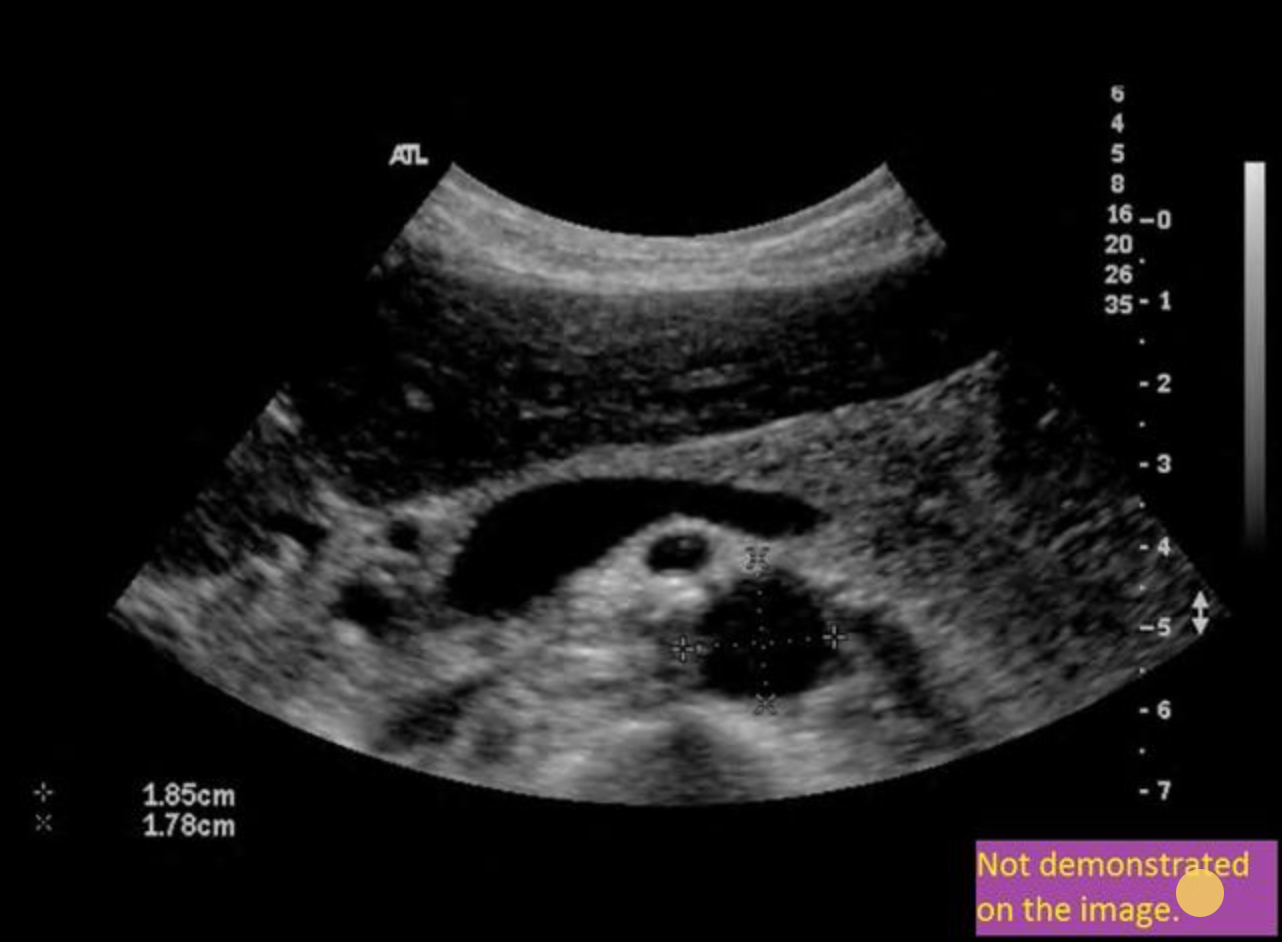

Use your mouse to place your cursor over the superior mesenteric vein and click to mark the vessel if the vessel is not demonstrated on the image, mark the purple box that says “not demonstrated on the angle”.